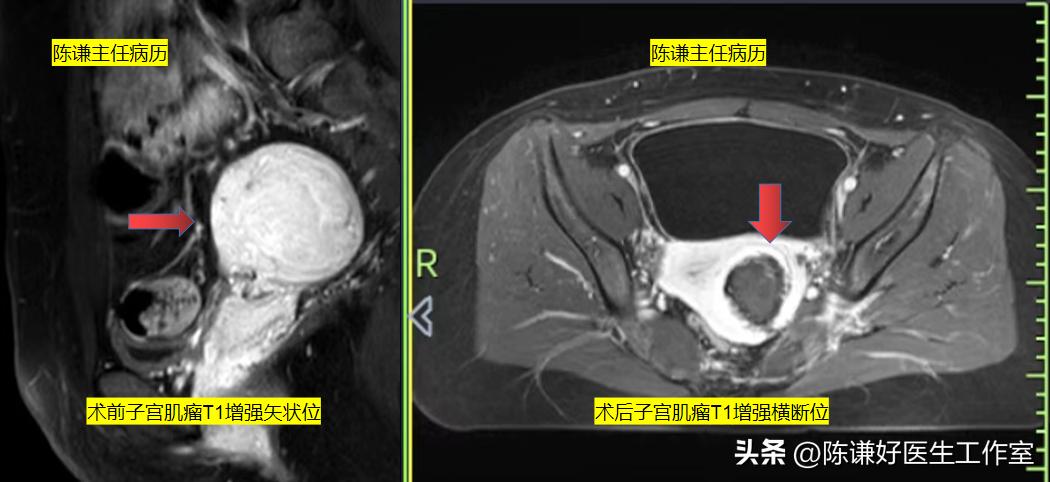

患者昨日在镇静镇痛下进行了海扶刀消融治疗,整个治疗过程中,患者几乎没有特别感觉,术中显示肌瘤坏死超声对比也很明显,术后第二天复查,显示整个肌瘤都已经消融,患者也几乎没有特殊不适,第二天就可以正常出院。

海扶治疗后增强磁共振术前术后对比